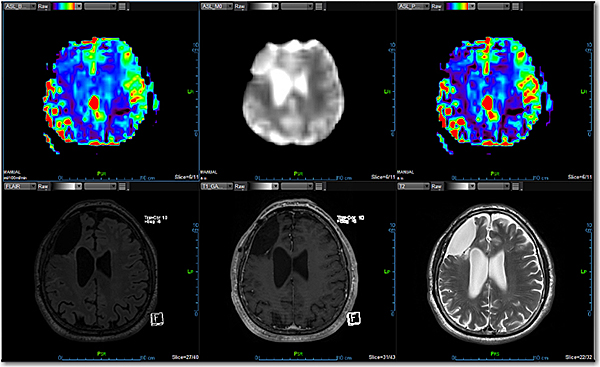

Додаток MR Neuro ASL

Додаток Neuro Arterial Spin Labeling (ASL) інтегровано в розширену візуалізацію Vitrea і забезпечує неінвазивне зображення для ефективного вимірювання перфузії.

Кількісне вимірювання мозкового кровотоку ASL без введення контрастної речовини та без випромінювання є ключовим компонентом педіатричної візуалізації

Має перевагу перед методами на основі контрастних препаратів для пацієнтів, які мають протипоказання для введення контрастних речовин

Дозволяє завантажувати повторні мітки та контрольні зображення та виконує 2D корекцію руху для вирівнювання повторних переглядів

Використовує просторове згладжування зображень для збільшення співвідношення сигнал/шум

Включає кількісне визначення ASL кровотоку за допомогою Mo